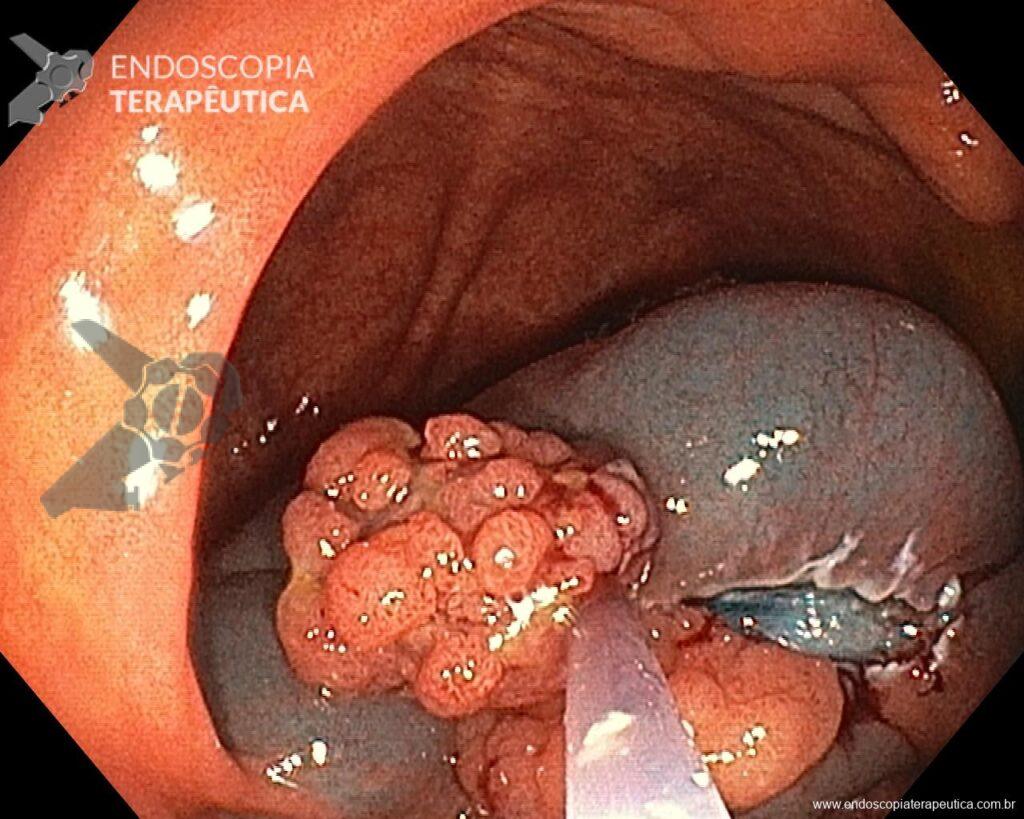

Una vez elegida la técnica de EPMR, tenga en mente que el objetivo debe ser la remoción completa de la lesión con la mayor seguridad posible. Para eso, la estrategia correcta es fundamental: no haga la burbuja submucosa toda de una vez, en vez de eso, haga inyecciones sucesivas seguidas del corte, preferentemente en el sentido proximal-distal; siempre que disponible, dé preferencia a soluciones viscosas, que garanticen una mayor patencia de la burbuja; utilice un asa más pequeña (10-15 mm) para sujetar la ampolla formulada; además de facilitar la operación, reduce el riesgo de perforación al intentar sujetar toda la lesión inadvertidamente.